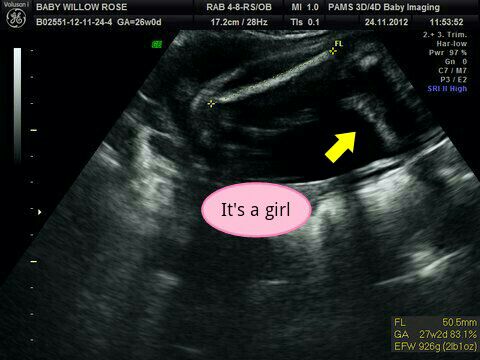

confirmed girl 26wks :)

This is my little girls confirmed potty shot at 26wks :) I had 100% girl guesses on my nub shot and a confirmation at my 20wk scan but I needed extra reassurance so had a 3d/4d scan to confirm! Tech was 99.9% positive she's all girl! :) xx

I love that the scan even has her name on it!